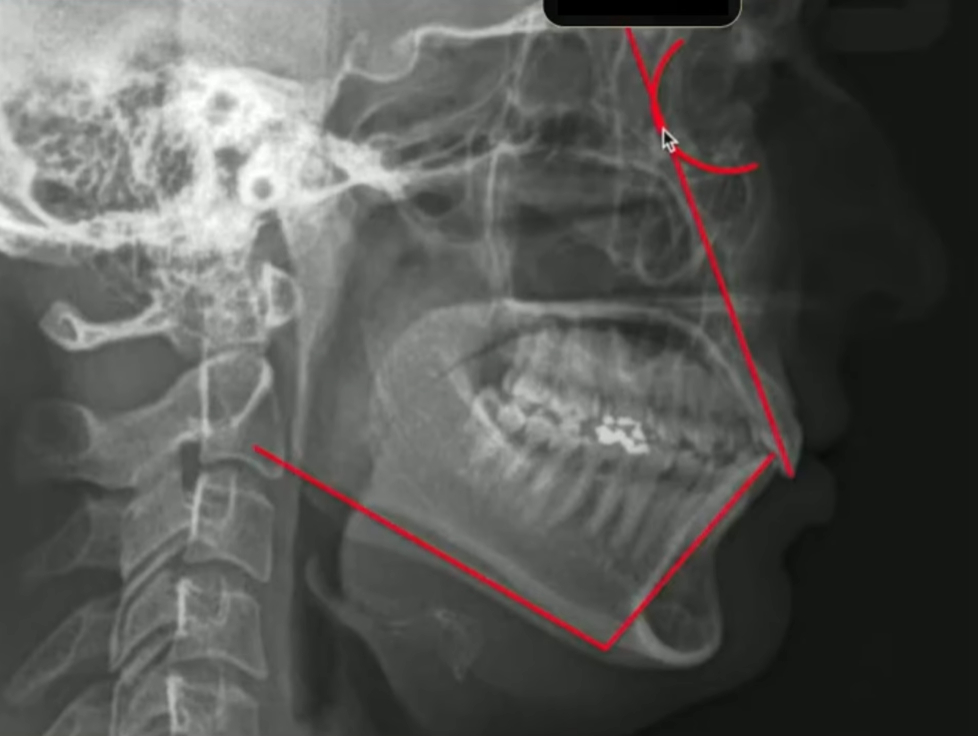

Todo mundo aqui consegue ver bonitinho que os incisivos tanto superiores quanto inferiores, eles estão inclinados para vestibular:

Então nós estamos diante de uma paciente biprotrusa com incisivos inclinados para vestibular

E aqui eu tiro a prova dos 9, eu tenho certeza absoluta que esse incisivo está vestibularizado porque eu tracei o longo eixo dele, ele passou muito atrás dessa órbita:

E eu também consigo traçar o meu incisivo inferior, medindo ele com a base mandibular:

Quando eu faço essa medida do incisivo inferior com a base mandibular, qual a minha intenção?

Eu quero saber também se esse incisivo inferior está mais ou menos com 90 graus em relação à base mandibular, nesse caso aqui eu tenho os incisivos bem vestibularizados.